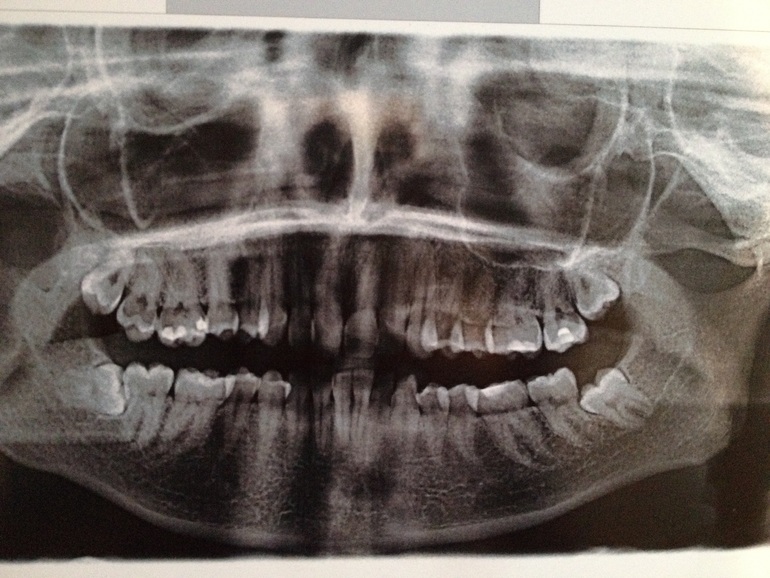

Фото с тем, что было у меня нет, потому что улыбалась не показывая кривизну своих зубов. Но при улыбке даже губа была неровной из-за клыков. Есть панорамный снимок, на нем видна вся 'красота' лежачих зубов мудрости и остальных зубов:

Удалив все зубы мудрости все еще сидящие у меня в деснах к 23 годам, я поняла, что после таких операций больше мне ничего не страшно)))и установила брекеты, самые простые.